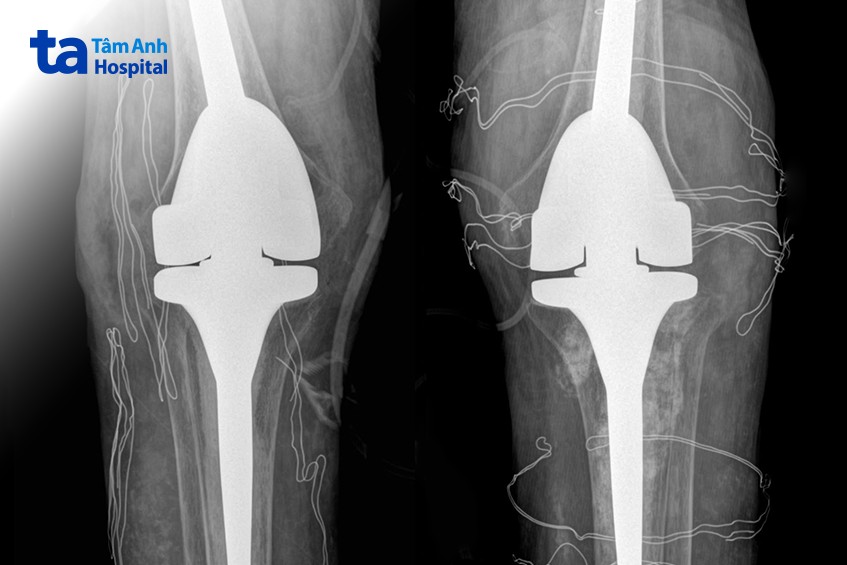

ThS.BS Nguyễn Quang Tôn Quyền, Phó khoa Chấn thương Chỉnh hình, Bệnh viện Đa khoa Tâm Anh Hà Nội chẩn đoán anh Tiến mất khả năng duỗi khớp gối, chỉ co được 60-70 độ, chụp X-quang cho thấy hai khớp gối bệnh nhân biến dạng nặng, tổn thương tophi khiến khớp và xương tiêu. Kiểm tra loại “thuốc” mua trên mạng mà anh Tiến uống, bác sĩ phát hiện là sản phẩm hỗ trợ sức khỏe đã bị Cục Quản lý Thực phẩm và Dược phẩm Mỹ (FDA) cảnh báo chứa chất dexamethasone gây nguy hiểm.

Anh Tiến được chỉ định phẫu thuật thay khớp nhân tạo. Xét nghiệm máu trước mổ cho thấy nồng độ cortisol và ACTH (hormone kích thích tuyến thượng thận sản xuất cortisol) thấp. Bác sĩ Quyền chẩn đoán bệnh nhân bị suy tuyến thượng thận do lạm dụng chất dexamethasone dài ngày.

Êkíp bác sĩ loại bỏ các hạt tophi gây cản trở vận động, thay thế khớp gối đã tổn thương bằng loại khớp nhân tạo có bản lề, dành riêng cho bệnh nhân có các biến dạng khớp nghiêm trọng. Hậu phẫu, anh Tiến tiếp tục truyền thuốc ổn định nồng độ hormone tuyến thượng thận trong 2 ngày, sau đó duy trì uống thuốc hormone thay thế.